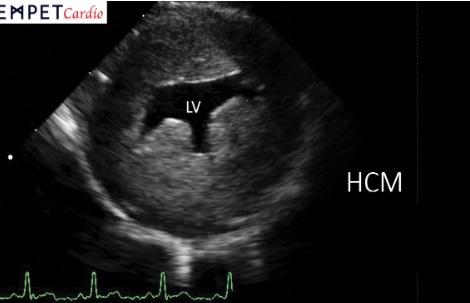

Katter med HCM har tykkere muskelvegg i hjertet enn friske katter og dette kan etter hvert gå utover hjertets funksjon. HCM kan føre til hjertesvikt med væske i og rundt lungene slik at det blir vanskelig for katten å puste.

For å stille diagnosen HCM, utfører en veterinær kardiolog en ultralydundersøkelse av hjertet. Dette gjøres stort sett uten bedøvelse, og medfører ingen smerte for katten. Undersøkelsen gir deg som dyreeier informasjon om diagnose, sykdomsgrad og risiko for utvikling av komplikasjoner som blodpropp og hjertesvikt. Hos godt voksne katter kan det være aktuelt å sjekke stoffskiftet med blodprøver samt å måle blodtrykk. Det er ingen medisiner eller operasjoner som kan gjøre katter med HCM friske, men selv de som har utviklet hjertesvikt kan leve et godt liv i opp til et par år så lenge de får riktig medisinering og oppfølgning. Vi anbefaler årlig hjerteundersøkelse av katter som har fått diagnosen HCM.